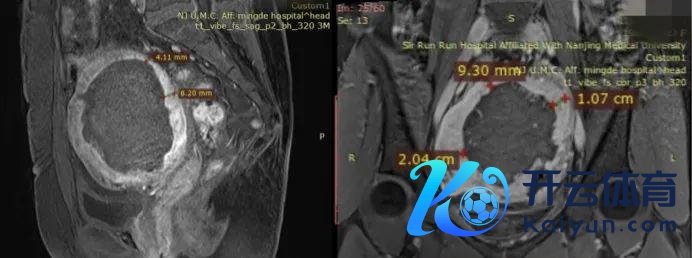

研究到她不肯意子宫切除,咱们经受给她作念超微创的经皮微波消融治愈,经由治愈之后,下方的图是她消融之后的罢休,从增强核磁共振的情况来看,腺肌症病灶基本上被浪漫了(图内部黑影的部分,代表着坏死),作念消融治愈的同期咱们放了曼月乐环谛视后续的复发。

在这次治愈之后,她的痛经透彻隐没,月事量也变得相配少。所幸到本年还一直莫得痛经,前些天来找我复查,超声评估下来,子宫还是松开到了71*69*69mm(经线较前松开了一半以上),可是不好的是这次她子宫前壁厚度加多了,当今前壁厚36mm,后壁厚度35mm。